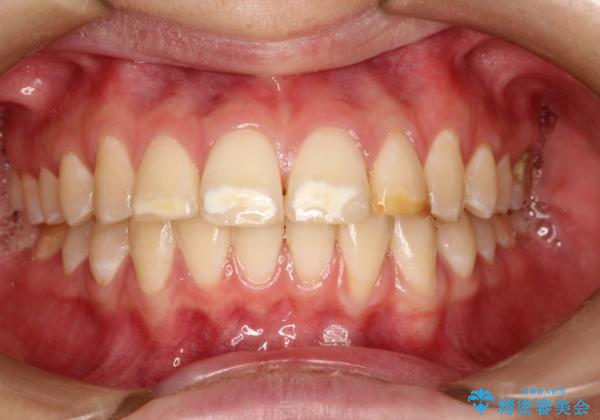

- 前歯をきれいにしたいとのご希望がありました。

生まれつき歯の色が白濁しているところや、黄色くなっているところがあり、セラミッククラウンに審美的改善を行うこととしました。

ご自身の歯を削る必要がありましたが、セラミッククラウンを装着することで、審美的改善ができました。